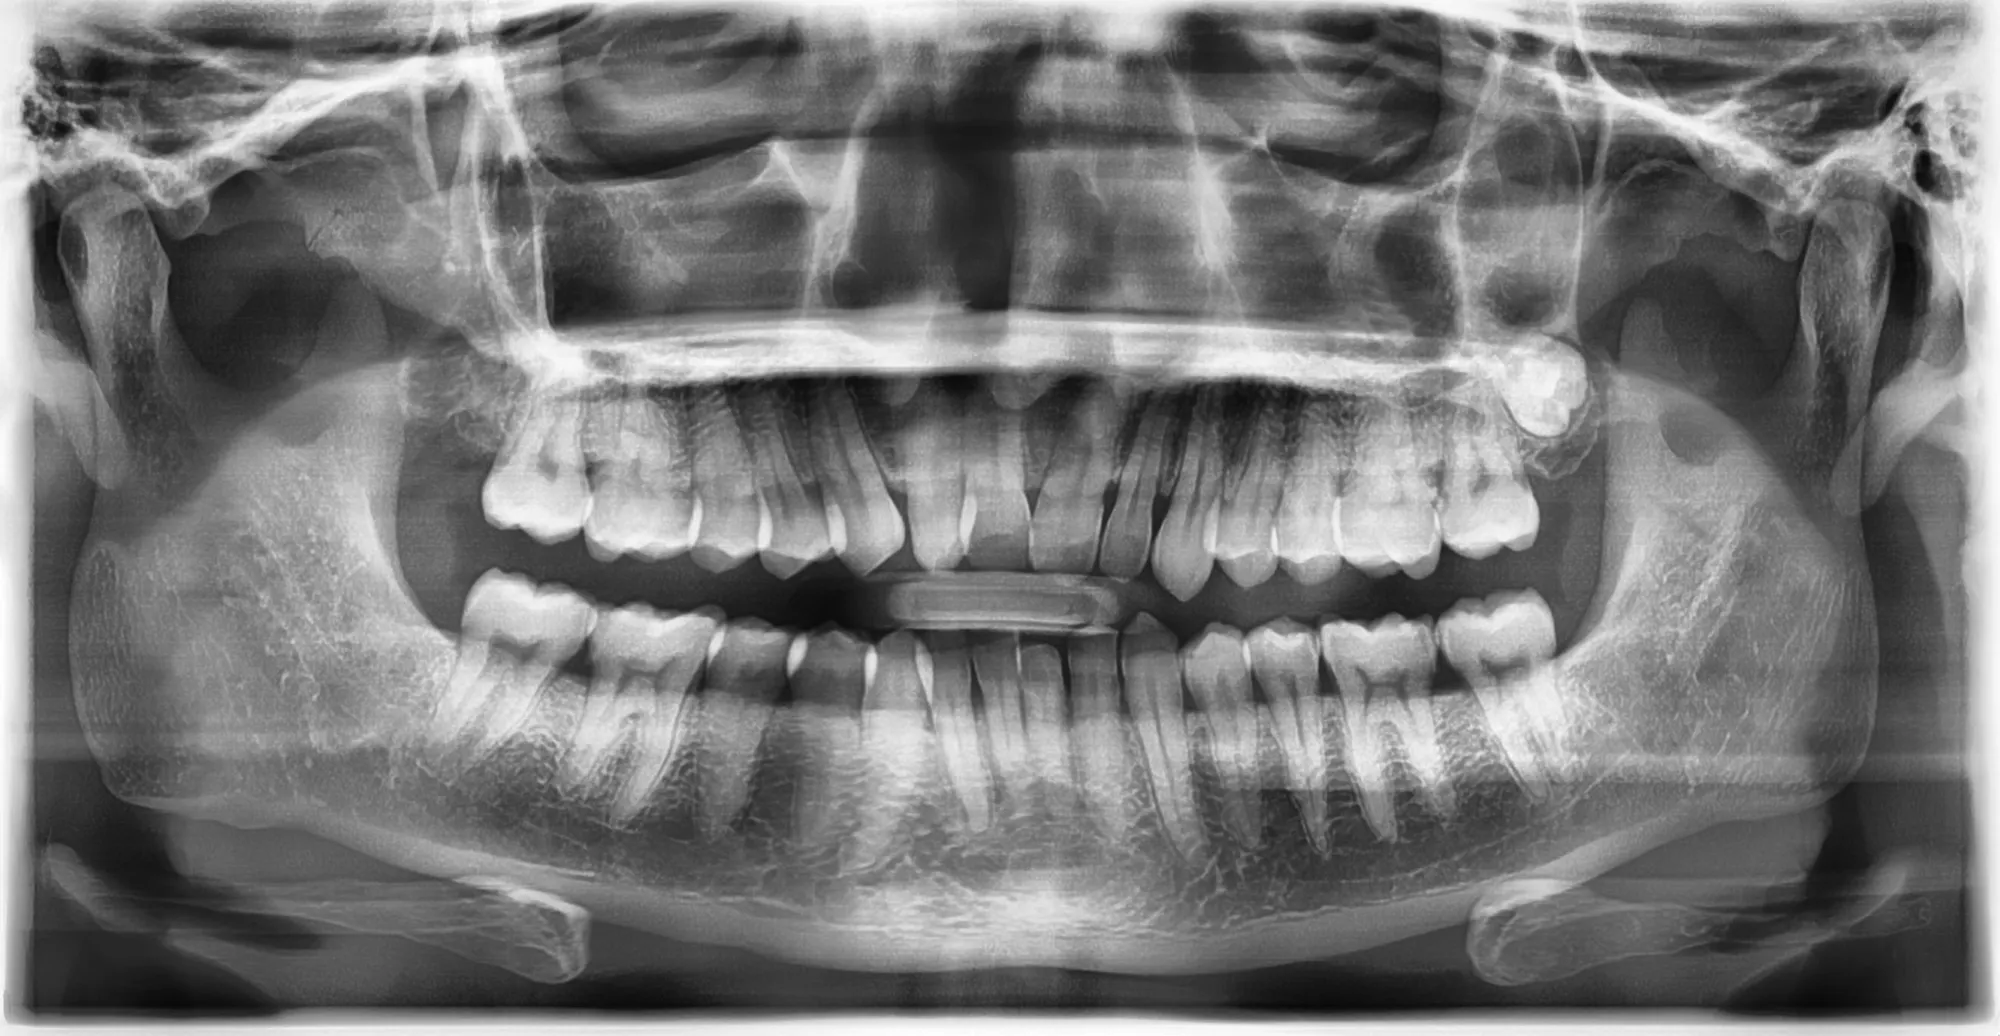

Dopo un’attenta diagnosi radiografica, la procedura viene eseguita in anestesia locale e con la possibilità di sedazione cosciente per i pazienti più ansiosi.

I denti del giudizio possono causare problemi quando sono inclusi o crescono in modo errato, provocando dolore, infiammazione e rischio di infezioni. L’estrazione viene eseguita con tecniche avanzate per garantire il minimo disagio e un recupero rapido.

- Se i denti del giudizio sono inclusi o parzialmente erotti.

- Se causano infiammazioni gengivali ricorrenti.

- Se compromettono l’allineamento degli altri denti.